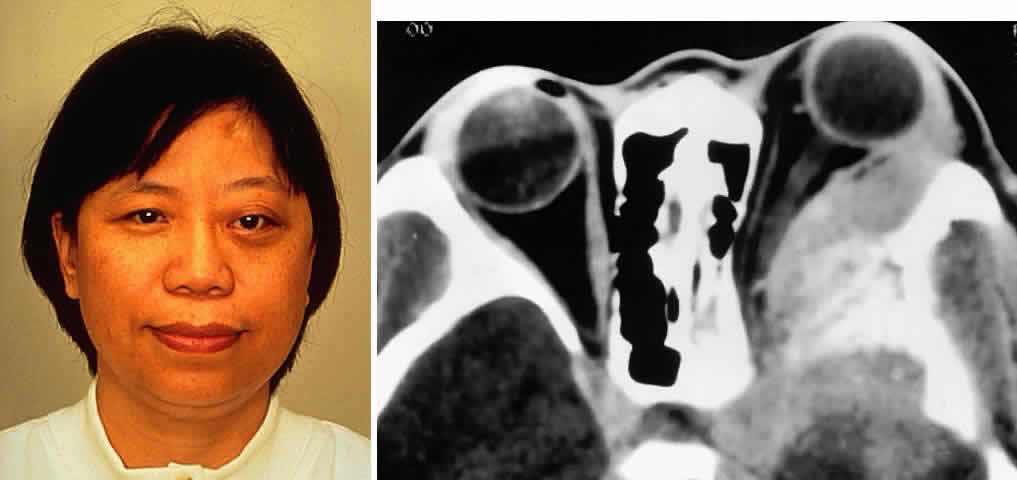

Extrascleral extension occurs in 10% to 15% of patients with uveal melanomas118–120 and may present clinically as a visible anterior nodule, as proptosis in patients with known intraocular tumor (Fig. 13), with phthisis and unsuspected tumor, or as a mass in orbital recurrence. Orbital recurrence associated with hepatic metastasis has been described as late as 42 years after primary enucleation.121 Orbital extension may only become evident at the time of surgery; however, the use of ultrasonography and CT scan may lead to increasing preoperative detection of extrascleral nodules.

Fig. 13. A 65-year-old man presented originally with a right retinal detachment and secondary glaucoma due to a large choroidal melanoma. The patient refused enucleation and self-treated instead with herbal medicines and “health foods.” He presented again 6 years later with acute onset of proptosis associated with pain, periocular edema, erythema, and marked restricted ductions (A). CT scan revealed the intraocular tumor, with massive orbital extension and displacement of the globe anteriorly, downward, and laterally (B and C). He underwent lid-splitting exenteration and split-thickness skin graft from the anterior thigh. The gross specimen shows the massive orbital component of melanoma, which had extended from the posterior choroid through emissarial vessels (D). An area of predominantly spindle-shaped melanoma cells with scattered, heavily pigmented macrophages is shown (E) (H & E, × 200). (D and E courtesy of Valerie A. White, MD, Department of Pathology, University of British Columbia, and the Vancouver Hospital and Health Sciences Center.)